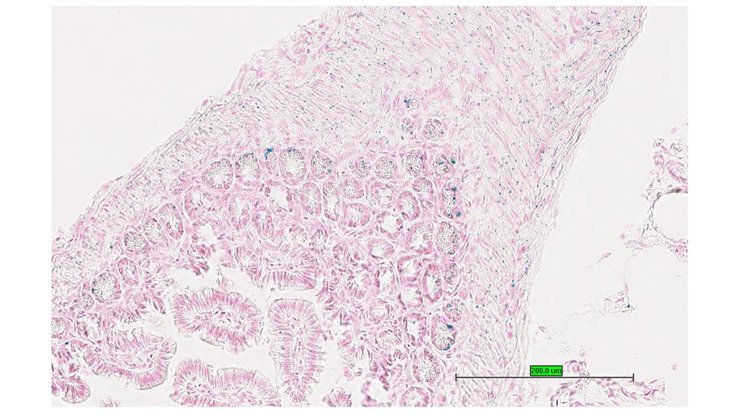

TS28: stomach Present UC Davis_1884594

Specimen UC Davis_1884595: postnatal adult; Bcs1ltm1.1(KOMP)Vlcg/Bcs1l+ (more )

TS28: stomach Present UC Davis_1884595

Specimen UC Davis_1884596: postnatal adult; Bcs1ltm1.1(KOMP)Vlcg/Bcs1l+ (more )

TS28: stomach Present UC Davis_1884596

TS28: stomach Present UC Davis_1884641

Specimen UC Davis_1884642: postnatal adult; Bcs1ltm1.1(KOMP)Vlcg/Bcs1l+ (more )

TS28: stomach Present UC Davis_1884642